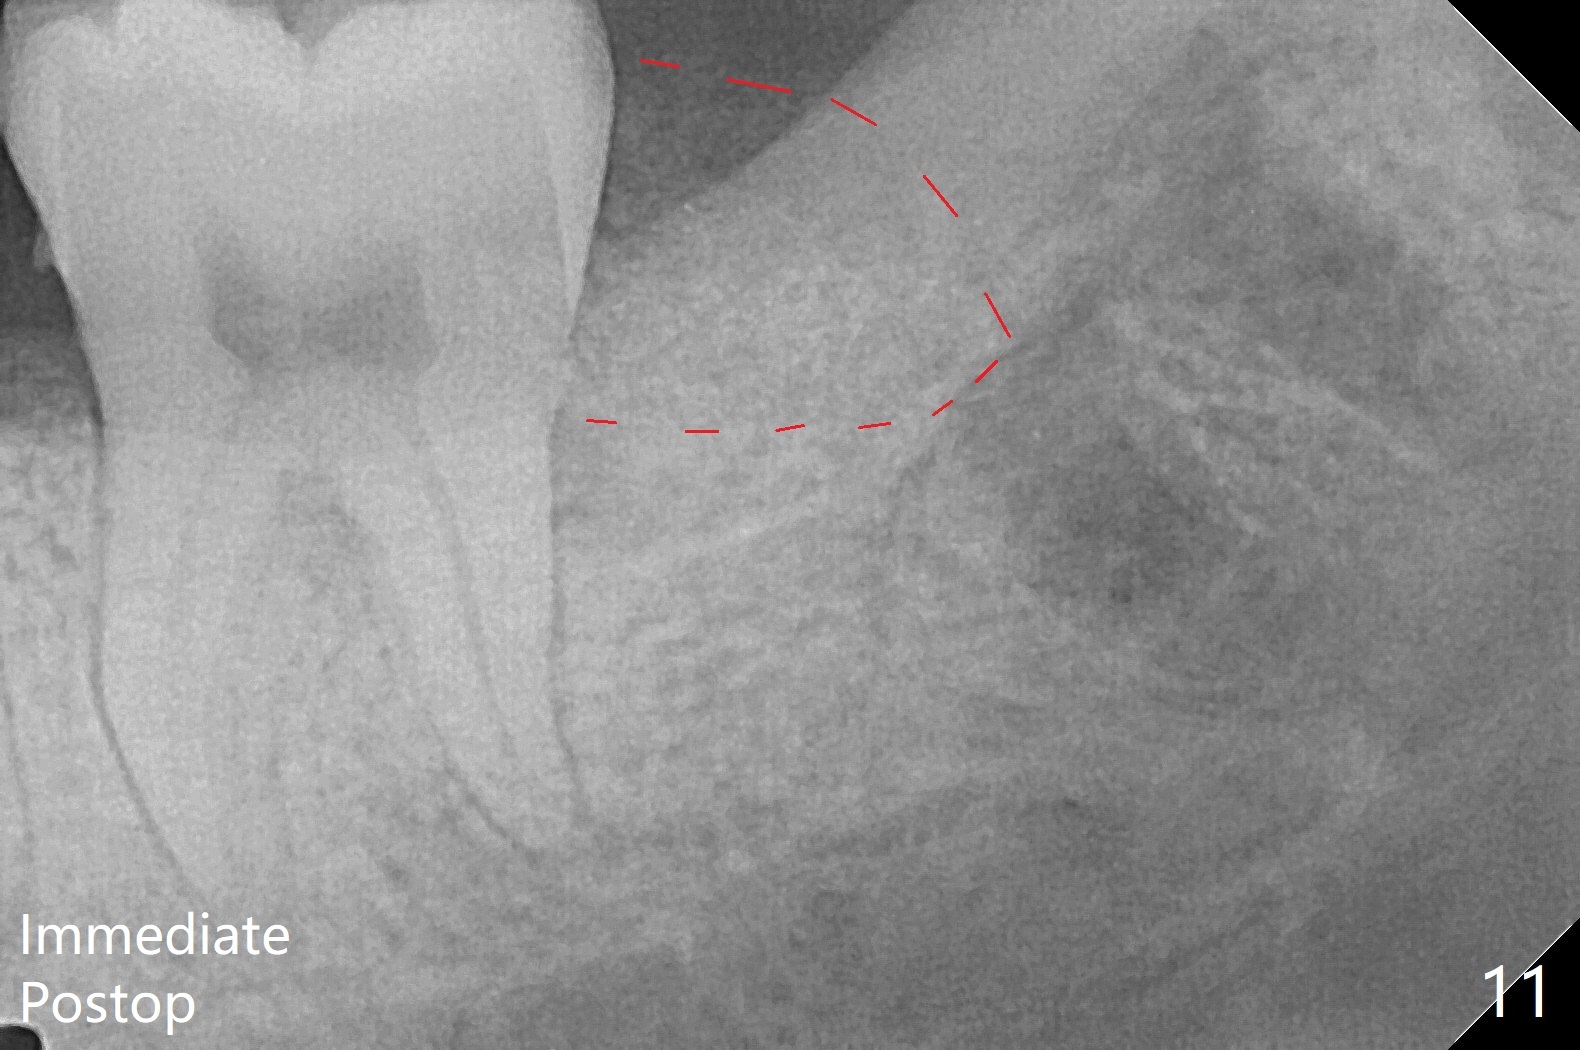

When the tooth #17 is extracted (Fig.9; 23 years old), collagen plug is inserted into the root portion of the sockets (Fig.10: 1 (white outline)), Vanilla graft is placed against the distal surface of #18 (2 (red outline)) and Osteogen plug (3 (green outline)) is placed coronally (3 steps). There is no bony defect associated with the distal surface of the tooth #18 immediate postop (Fig.11 (red dashed line: bone graft)). The wound heals in 2 weeks.